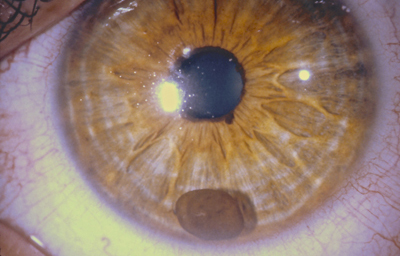

Aniridia completa, catarata y distrofia corneal de la aniridia

Archivo Dr. Francisco Barraquer

Caso de paciente con Coloboma en un ojo y Aniridia en el contralateral

OD

Archivo Fotográfico Dr. Francisco Barraquer

OI

Archivo Dr. Francisco Barraquer